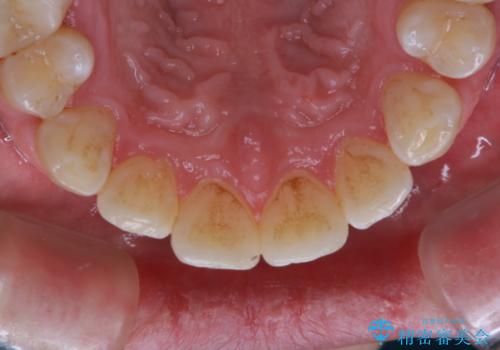

- 歯磨きをしても取れない汚れが気になるとのことで来院されました。PMTC60分コースを行いました。

着色や歯石は歯みがきで落とすことはできません。誤ったセルフケアを行うと、逆に歯の表面を傷つけてしまったり、トラブルを起こすこともあります。

着色や歯石が付着したままだと、居心地のよくなった細菌たちが口の中の栄養をたっぷり摂ってさらに付着しやすい状態となります。